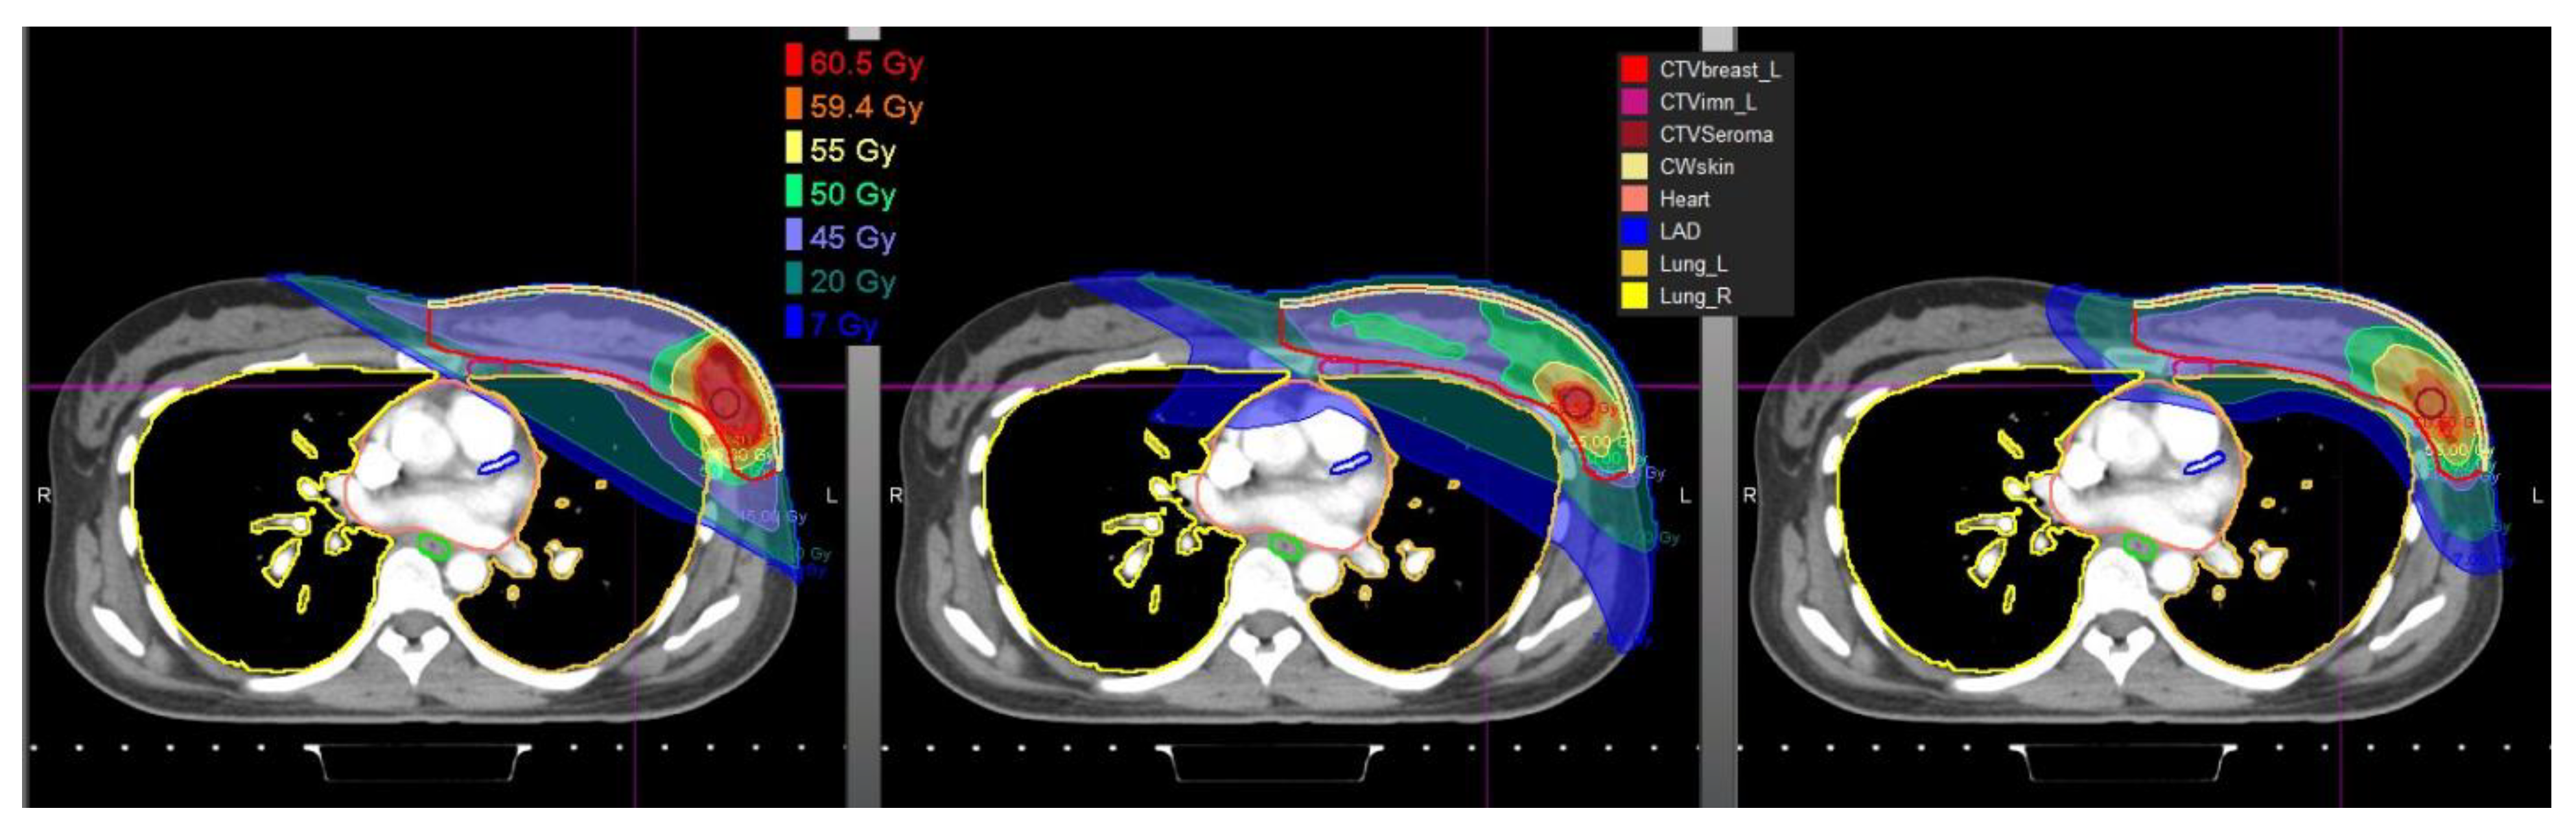

2.2. Cardiac Dose

2.3. Lung Dose